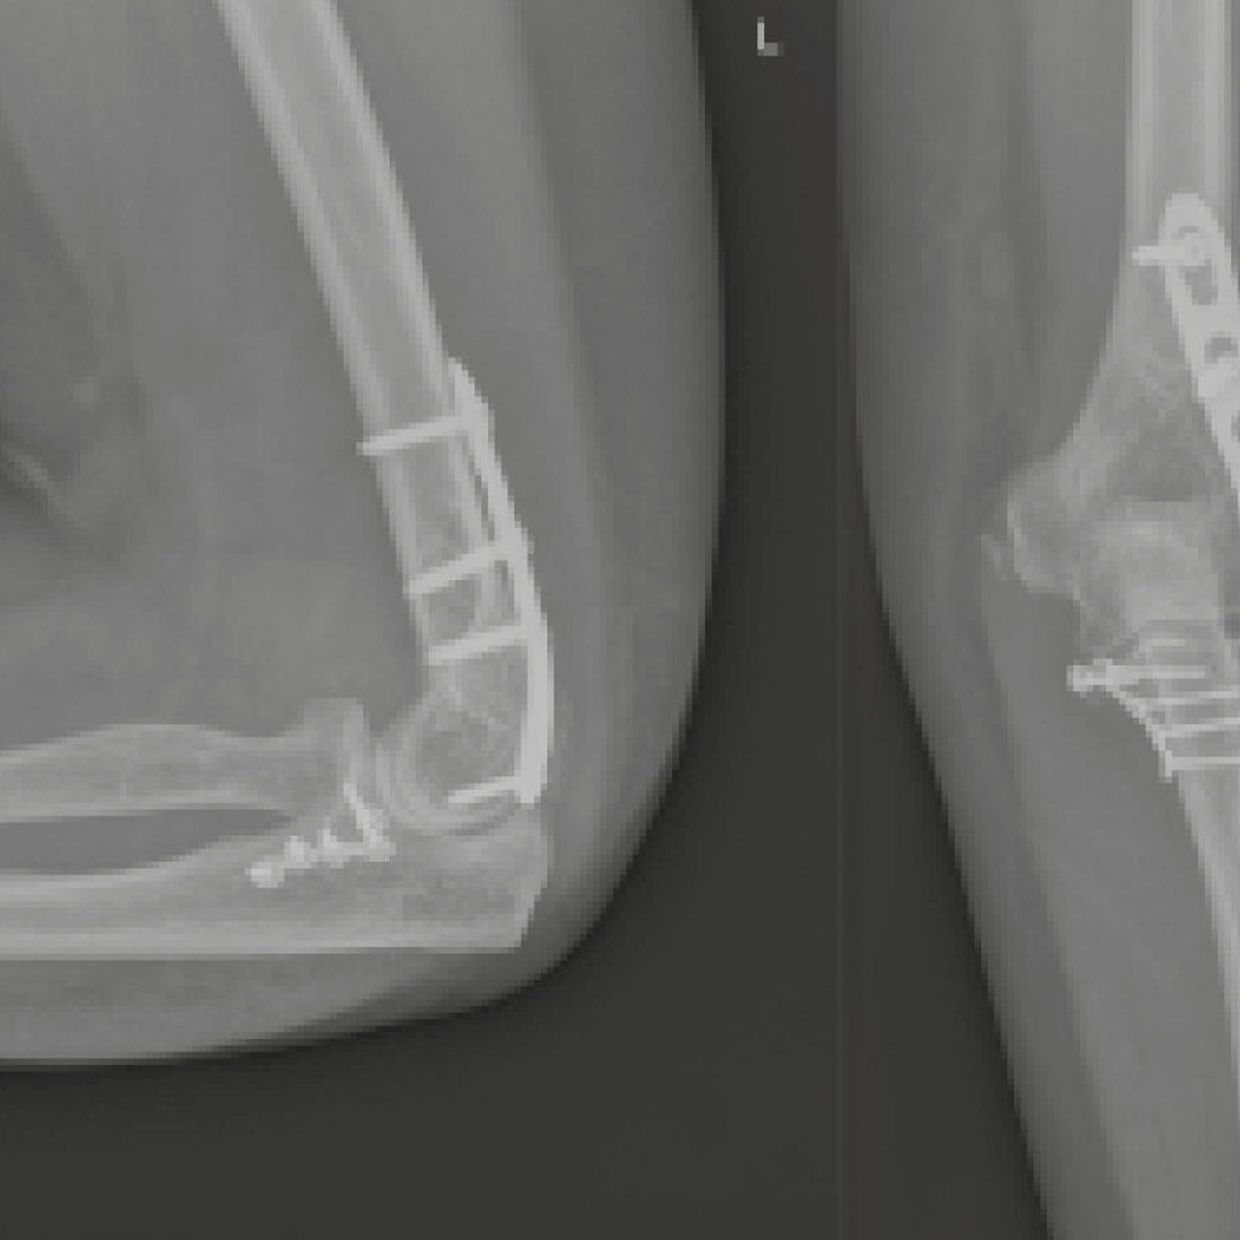

Radiuskopfbruch – Wikipedia